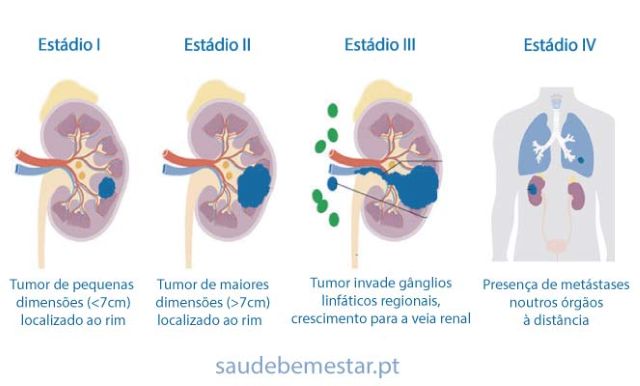

- Perfil dos pacientes — Predominantemente homens entre 50–70 anos; muitas vezes o diagnóstico ocorre incidentalmente após exames por outras razões.

- Um dos principais desafios é o diagnóstico tardio, que torna o tratamento mais oneroso e menos eficaz — tanto para o paciente quanto para o SUS.